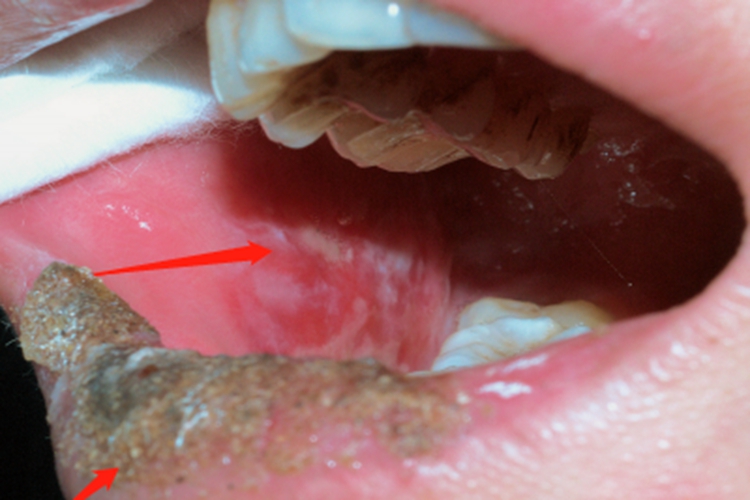

糜烂型口腔扁平苔藓可导致部分患者口腔出现珠光白色样条纹,触摸质地柔软有弹性,周围皮肤可发红,疼痛明显。部分患者嘴唇表面可伴有较厚的结痂,触摸粗糙。